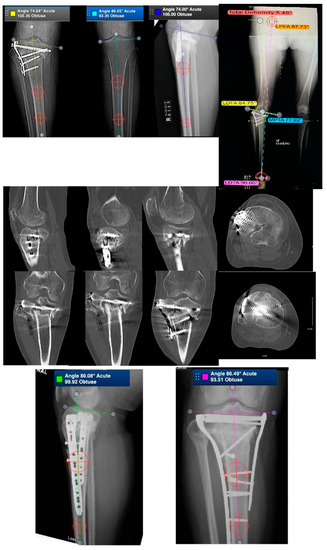

Det fanns fem rapporter om korrigering av felställning av medial tibial platå, alla enstaka fallrapporter. Skillnaden i dessa fall, gällande den laterala platån, är att ingen av dessa författare rapporterade en depression i platån. Alla hade felställning och varusvinkling av hela platån [12,13,15,16,17]. Varusvinklingen rapporterades som 7,8 grader, 9 grader, 9 grader, 15 grader och 25 grader. En sagittal flexionsdeformitet rapporterades också i tre fall av 2,6, 27 och 29 grader. Patienterna klagade över knäsmärta, effusion, knästrump och begränsat rörelseomfång. Patienterna utvärderades med långbensröntgen, datortomografi med rekonstruktion och, i två rapporter [14,16], 3D-modellering före osteotomin. Flera av författarna rekommenderade också en MR-undersökning för utvärdering av broskskador.

Korrektionerna beräknades med hjälp av stående filmer, och varje fall involverade en öppningskilosteotomi genom en medial parapatellär metod. Den mediala platån osteotomerades snett med ett signifikant benblock, och snittet gjordes antingen till tibialeminensen eller bara medialt om den. Deformiteten i koronalt och sagittalt plan korrigerades, tomrummet fylldes med kortikocancellöst transplantat och konstruktionen stöddes med en medial platta, vilket först beskrevs av Saengnipanthkul 2012 [18]. I en artikel följdes osteotomin av en knäprotes [19] på grund av den sena presentationen. Patienterna rapporterade goda till utmärkta resultat vid 5 månader [13], 6 månader [16], 12 månader [14] och vid 2 år [18] med smärtlindring, återgång av rörelseomfång och normal gång.

Fall av en 54-årig kvinna med intraartikulär (går in i leden)malunion av proximala tibia med 5 mm lateral depression och 13 graders varusdeformitet (första bildraden). CT-skanning visas i den andra bildraden. Patienten behandlades med en lateral parapatellär metod med en lateral tibial tuberkelosteotomi och en falluckosteotomi. De deprimerade fragmenten lyftes följt av en öppningskils tibialosteotomi. Mediala och laterala plattor applicerades för att hålla repositionen (tredje bildraden).

En posterior metod användes för att avlägsna fibrös vävnad och mobilisera det felaktigt förenade fragmentet. Ledkongruensen återställdes och fixationen säkrades med en posterior stödplatta och dragskruvar.